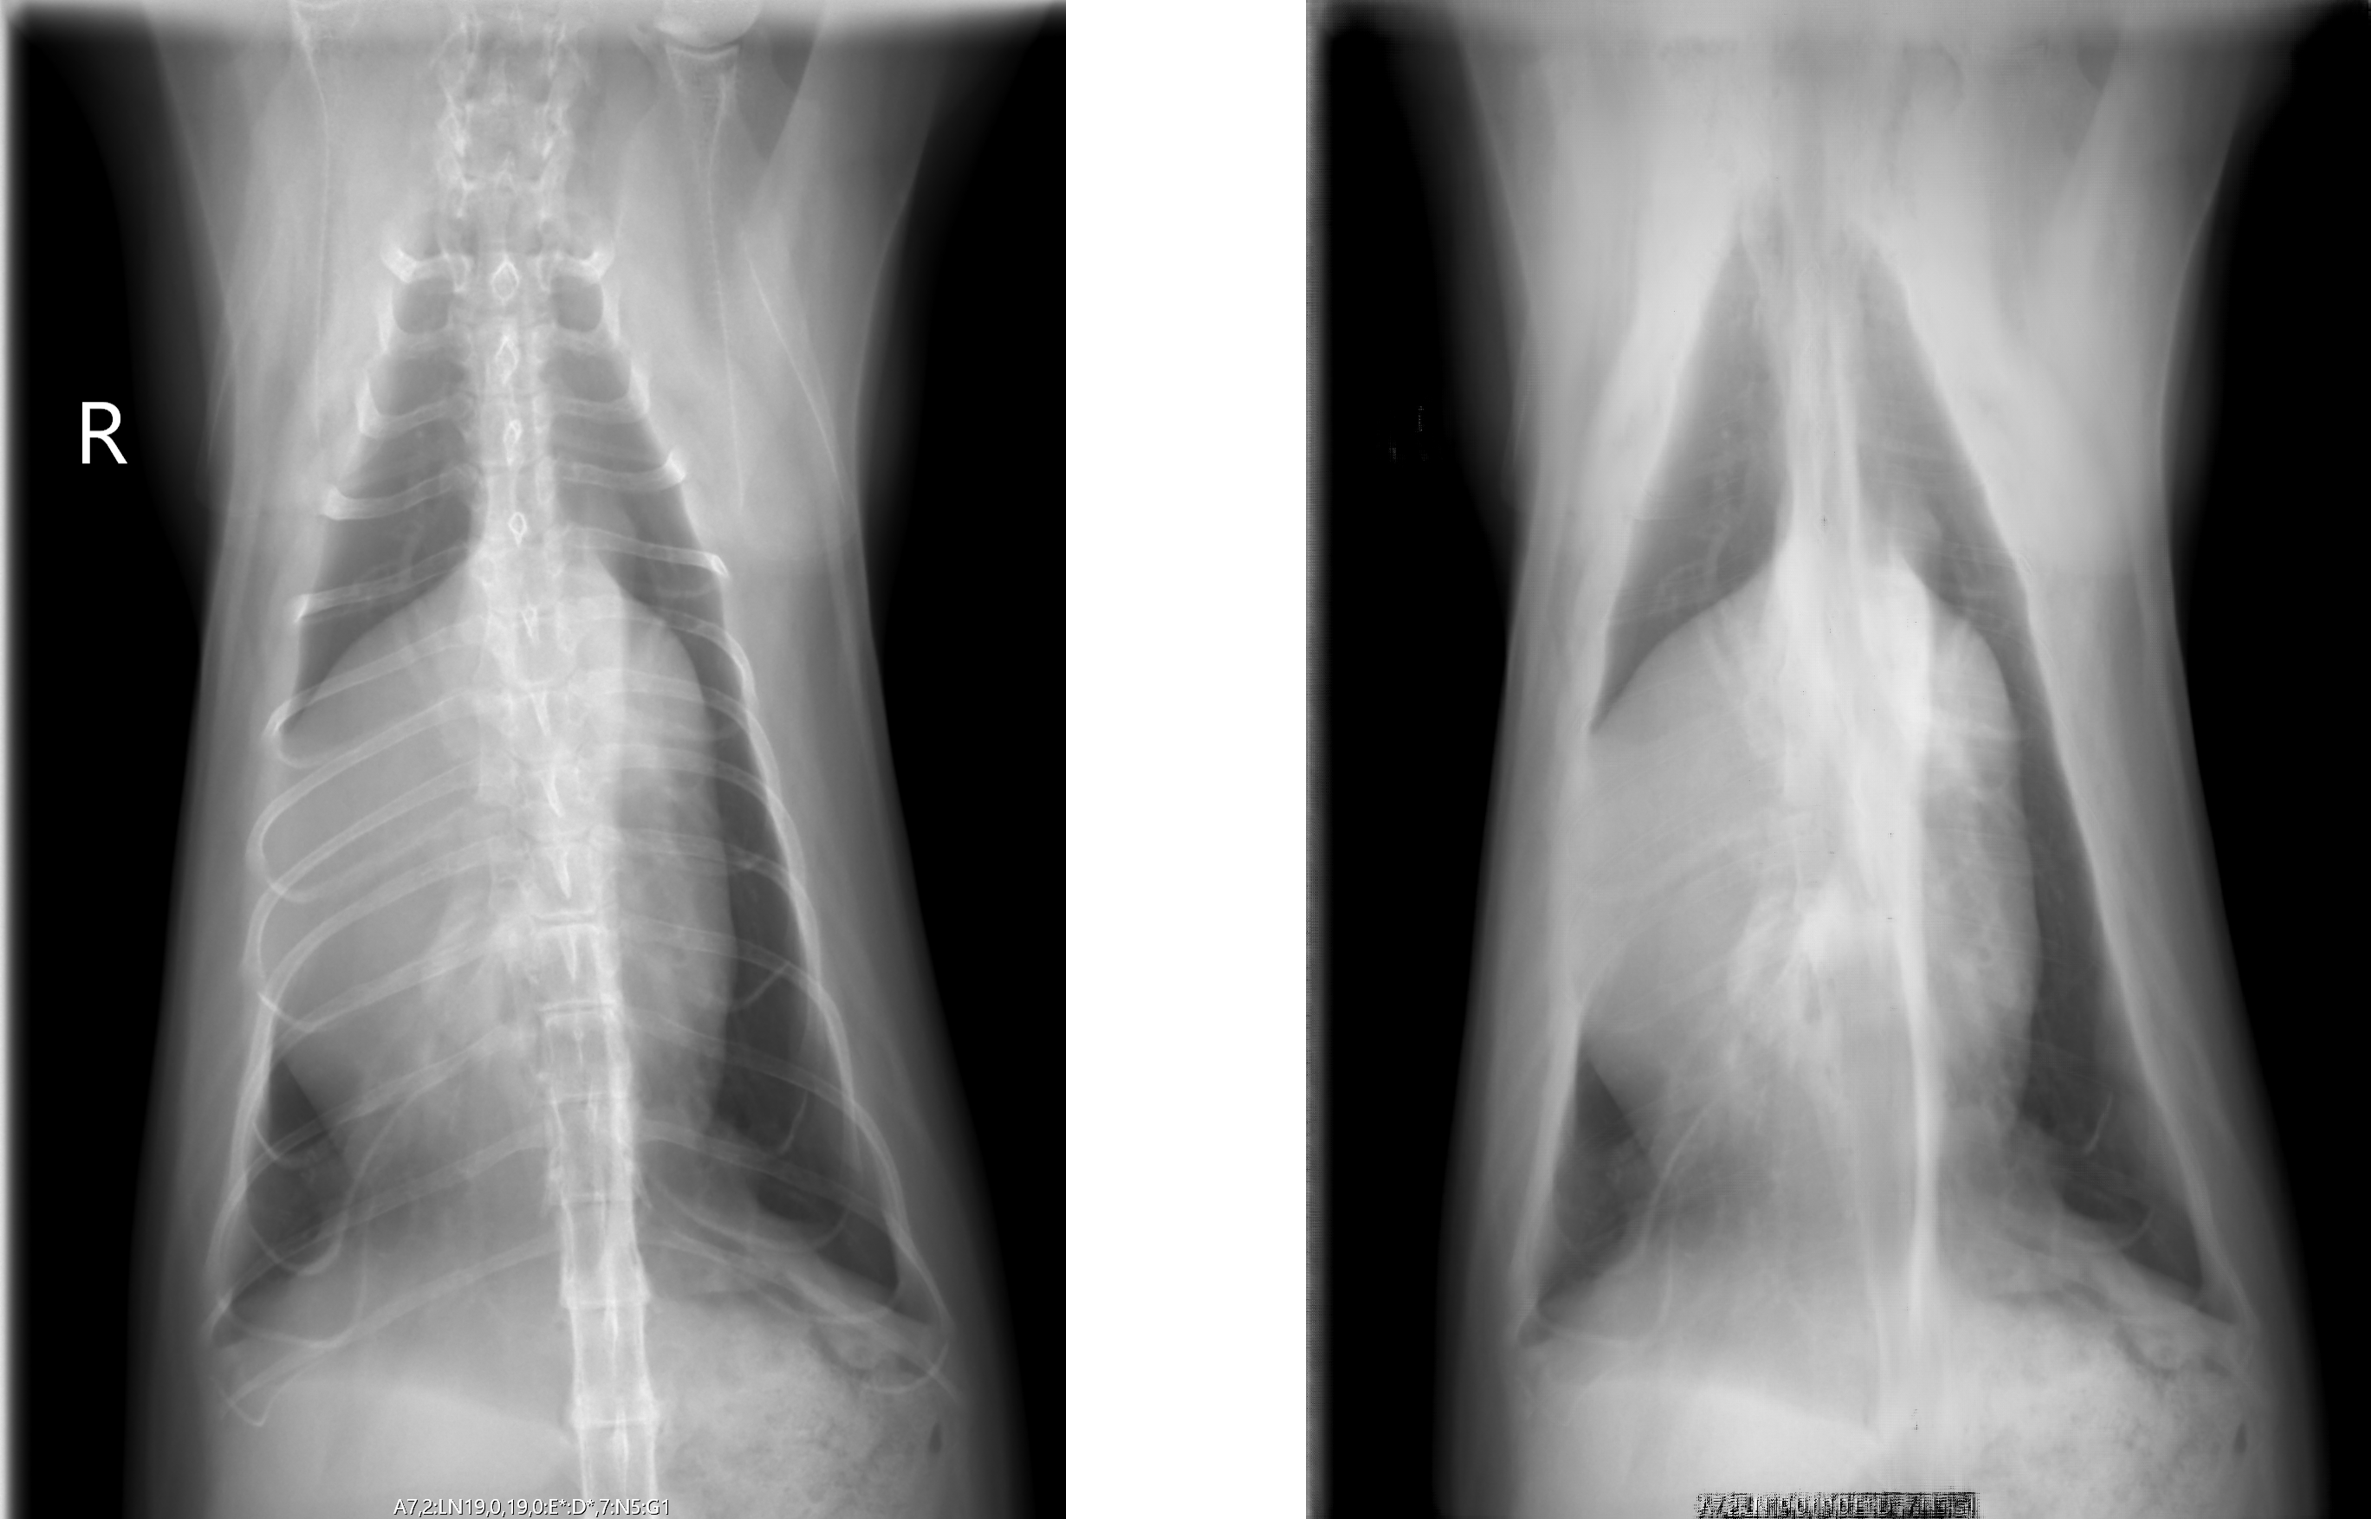

左) 猫のX線胸部画像 右) AIで骨を除去した画像

リッジアイと北大動物医療センターによる共同研究チームは、X線画像以外の医療画像を適切にX線画像と融合することで、”骨なしのX線画像” が欠如している状況でも、骨除去を行う機械学習モデルの開発に成功しました。

この技術により、獣医師がX線画像の読影を行う際に、骨以外の組織や病変に焦点を当てやすくなります。これは、獣医師の診断精度を向上させることにつながります。さらに、より早期の病気発見や治療に寄与することができます。特に胸部X線からの骨除去は、心臓疾患や呼吸器系の疾患など、様々な病状の診断に重要な役割を果たすことが期待されます。

リッジアイと北大動物医療センターは、今後もこの技術のさらなる研究と開発を進めていく予定です。これまで、猫の正面図のX線画像の骨除去技術の開発に成功しています。今後、猫の側面図への適用、さらには他の動物への適用も視野に入れ開発を継続し、本技術をより広範な状況で活用できるようにする予定です。